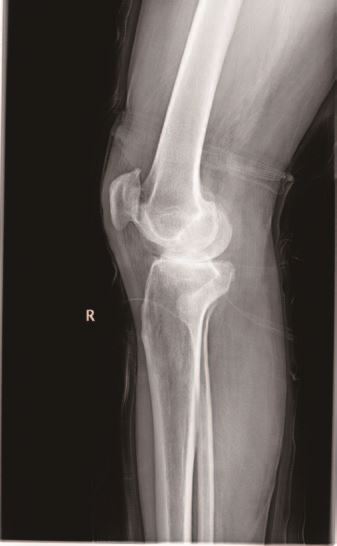

67岁的王大爷三年前出现右膝关节疼痛,经过多次口服药物、理疗等保守治疗,效果越来越不好,如今行走200-300米左右就疼痛难忍,严重影响日常生活,于是在家属的陪同下来到我院就诊。经X光片检查显示,王大爷术前膝关节活动度伸直5°,屈曲120°,轻度内翻畸形,被确诊为右膝骨性关节炎,医生建议手术治疗。5月20日,医生们为其实施了人工膝关节单髁置换手术,手术进行顺利,术后王大爷的手术切口愈合较好,膝关节内翻畸形纠正,1周内经过锻炼膝关节伸直5°,屈曲110°,王大爷对手术及术后功能恢复非常满意。